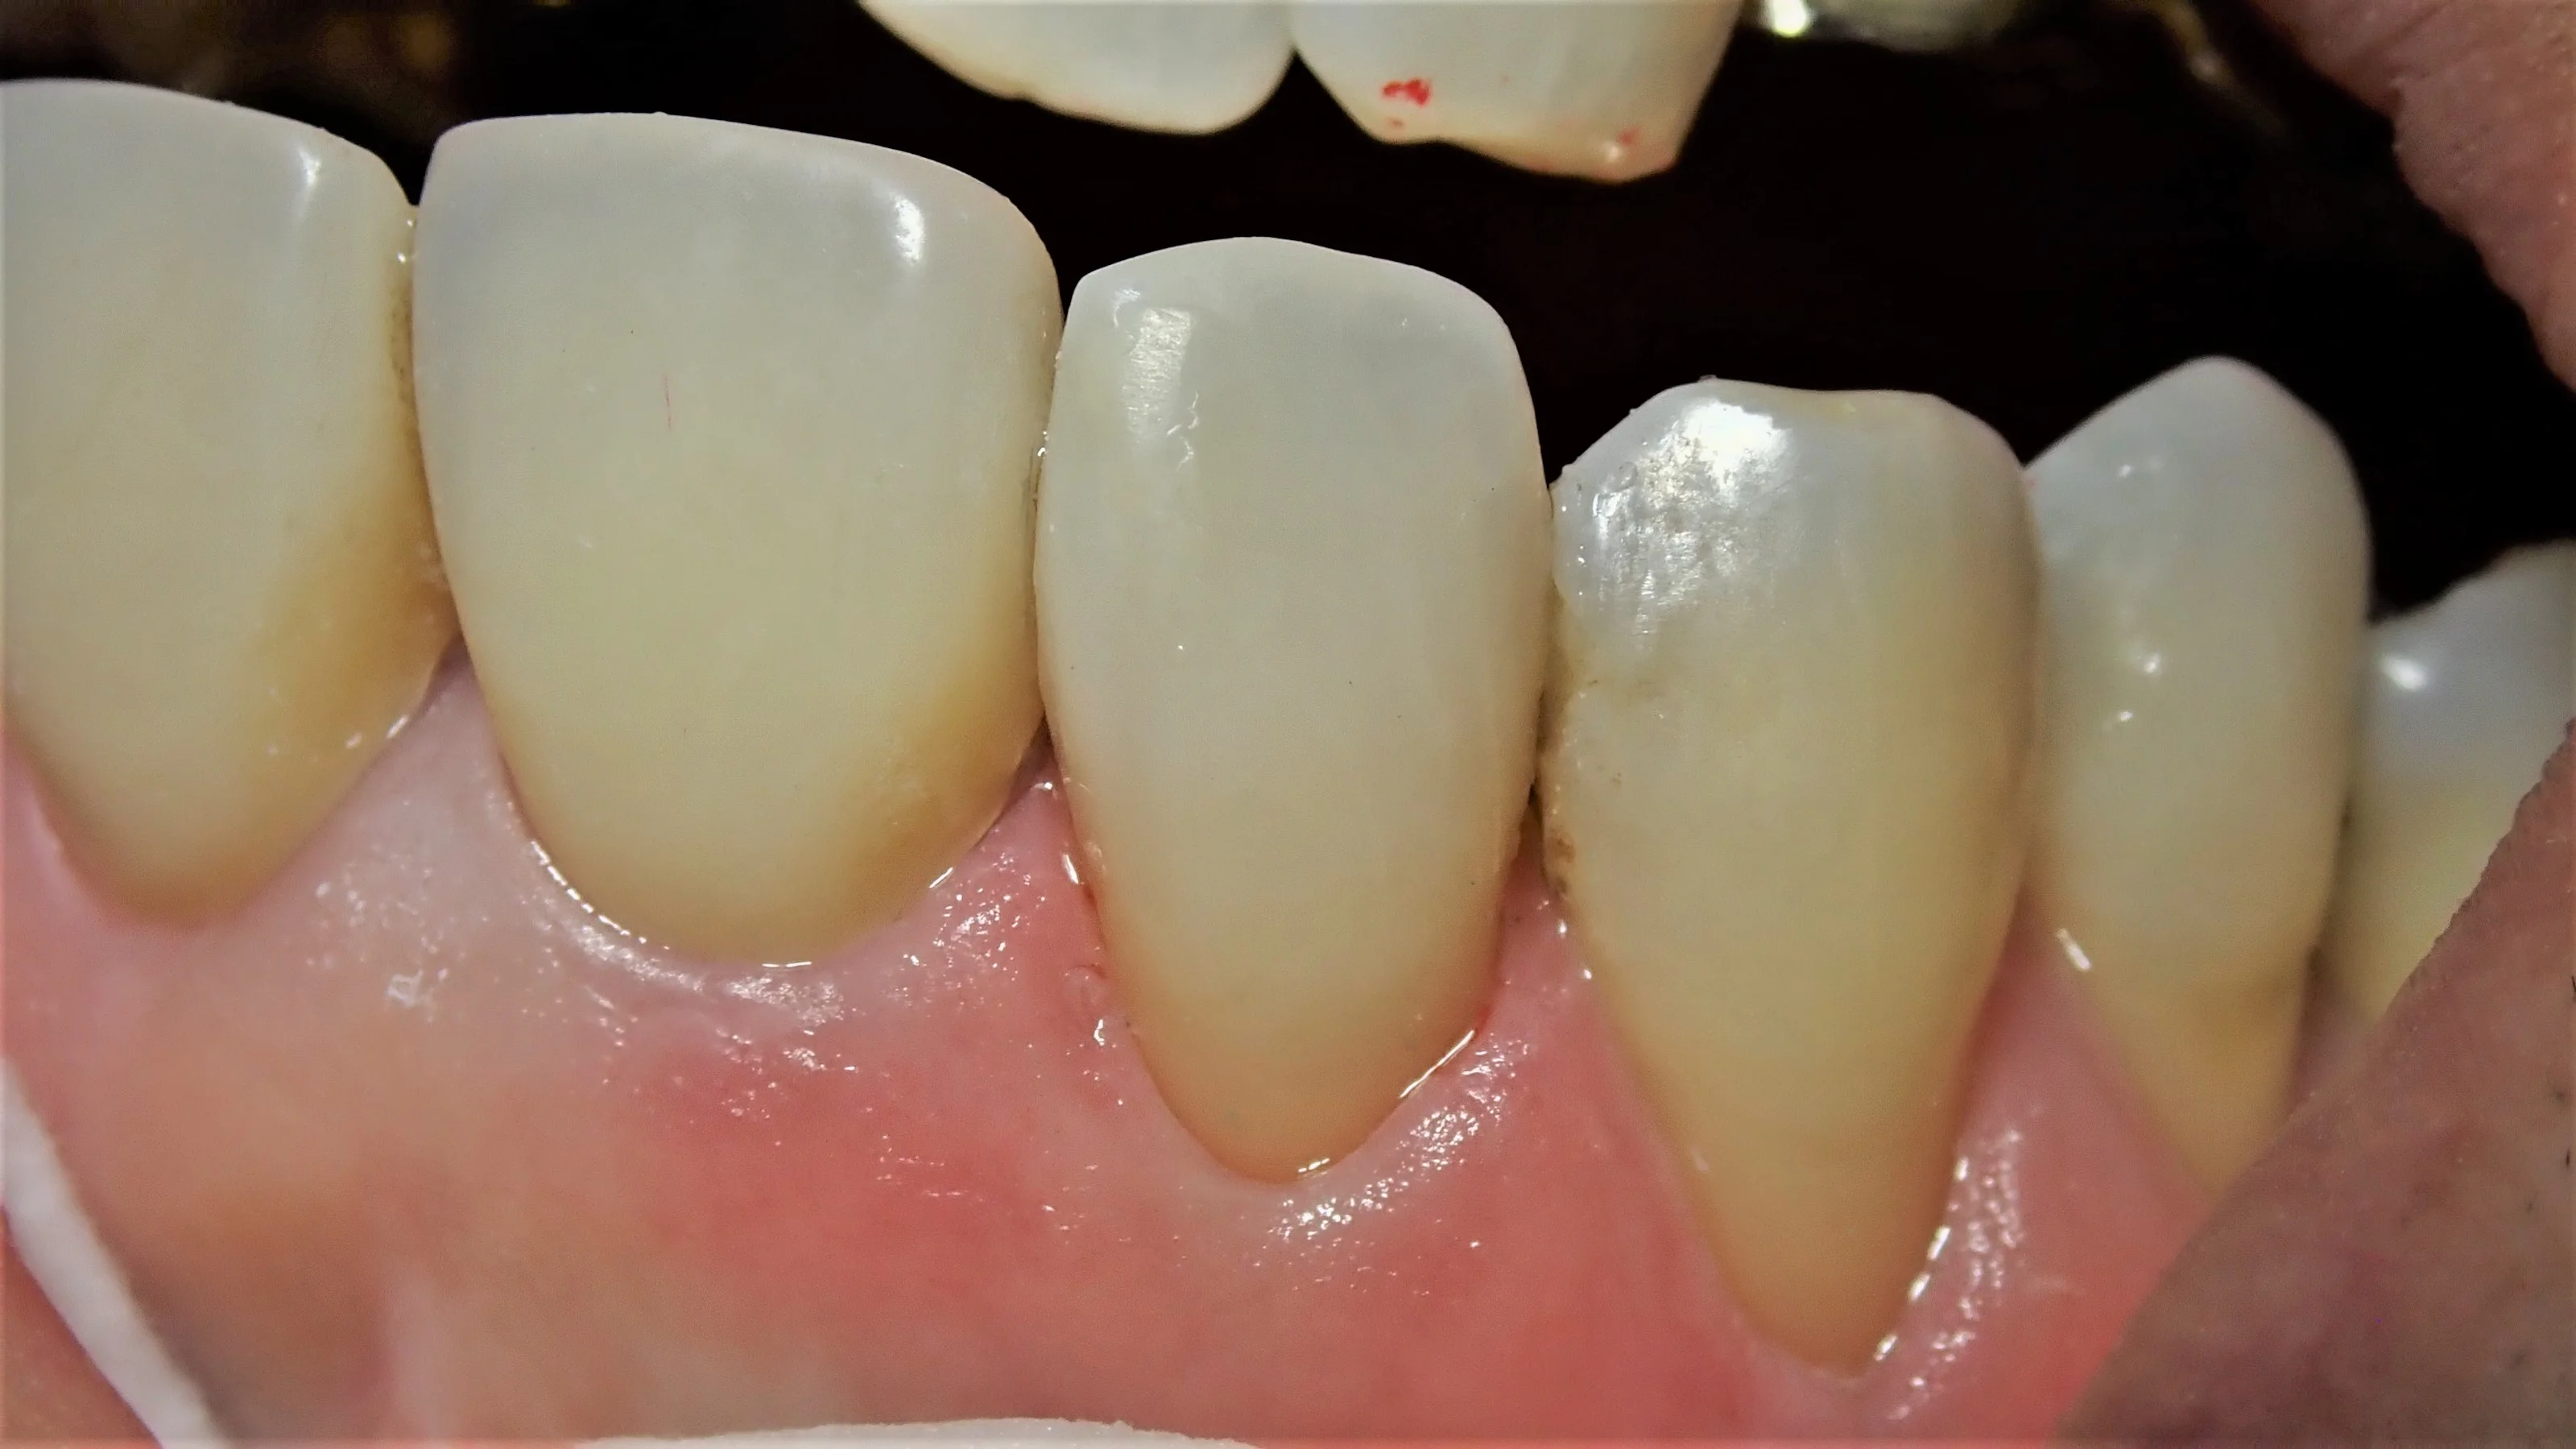

結果としては、

表側がこんな感じで

本来なら全周削って被せる「クラウン」形態になるような状況でしたが、無事に歯質を多く温存できたかと思います。